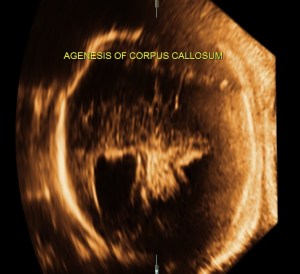

prominent ventriculomegaly of posterior horns of both lateral ventricles – colpocephaly

demonstration of both medial and lateral ventricular walls at a level where the single periventricular line is normally demonstrated

A specific diagnosis of agenesis of the corpus callosum has seldom been made before the third trimester, probably because the corpus callosum is not normally formed until 18 to 20 weeks43. Most authors agree that detection of agenesis of the corpus callosum is difficult prenatally, depending as it does on postnatal sonograms or CT or MR scans. In a series of seven fetuses with agenesis of the corpus callosum, Bertino et al35 reported that only three demonstrated a characteristic midline cyst. They described three findings that might lead one to suspect agenesis of the corpus callosum on routine transverse views:

- disproportionate enlargement of the occipital horn,

- demonstration of both medial and lateral ventricular walls at a level where the single periventricular line is normally demonstrated, and

- a more parallel course of both ventricular walls than normal.

They suggested that demonstration of these findings on axial views should stimulate additional coronal and sagittal views for evaluation of agenesis of the corpus callosum.

The increased separation of the normal-sized bodies and the enlargement of the atria and occipital horns of the lateral ventricle result in a typical ultrasound image. Upward displacement of the third ventricle is a very specific sign36 but presents only in 40% of fetuses.